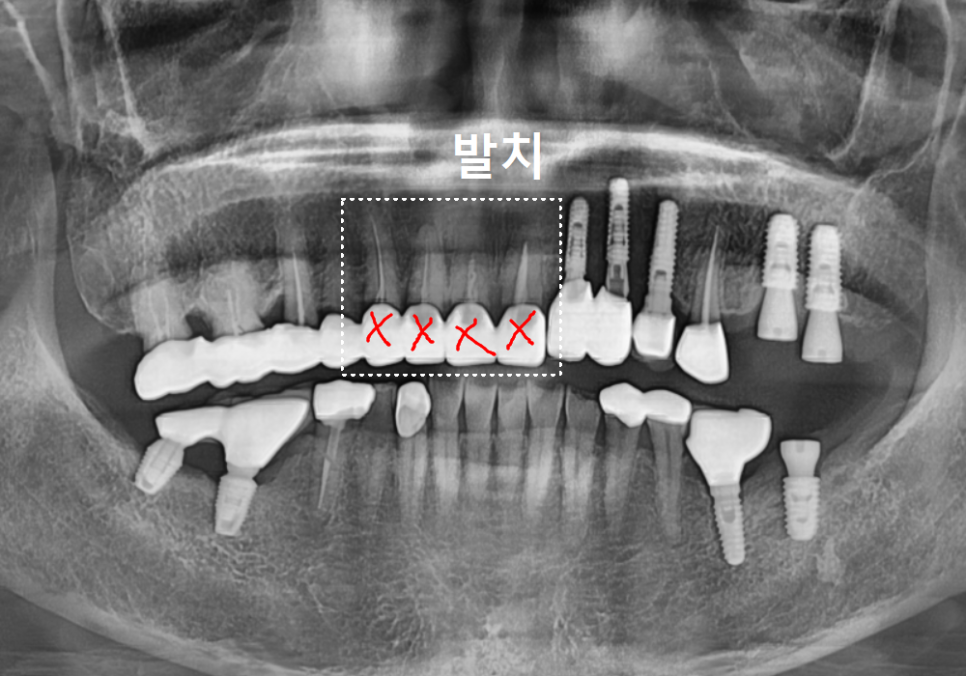

얼마 전, 3년 전에 하셨던

앞니 브릿지(#13~21)가 갑자기 빠져서

놀란 마음으로 내원하신 환자분이 계셨습니다.

빠진 브릿지를 제거하고 입안을

살펴보니 상황이 생각보다 좋지 않았는데요,

앞니 4개 모두 충치가 깊게 진행되어

검게 삭아버린 상태였고,

치료 계획

앞니 브릿지 탈락

결국 깊은 고민 끝에

상해버린 치아 4개를 발치하고,

임플란트 치료를 진행하기로 결정했습니다.